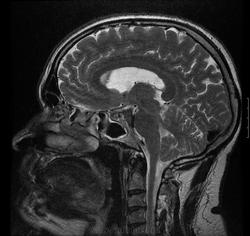

Смутил участок кзади от спинки седла по скату гиперинтенсивное на Т2, оттесняющий основную и ЗМА. Переделаю на 3 Тесла

По мне дык это перимезенцефалическое САК, что мы и видим на МРТ (как раз и аневризм не нашли). И гипертензия при САК - обычное явление. Как оно (кровоизлияние) повлияло на фистулу - не знаю, надо подумать, но способствовать могло. А стекания ликвора прекратились полностью?

Никогда не обращал внимание на форму глазных яблок.. Интересный момент. У меня были пациенты с атрофией зрительных нервов на фоне ВЧГ с очень даже красивыми глазами и наоборот. А как меняется форма глазных яблок? Я лишь обратил внимание на "тесное" БЗО и заострение миндаликов "peg-like"